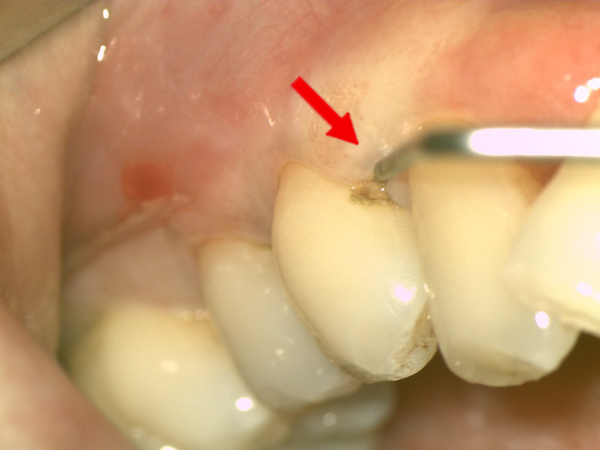

百雷射牙周治療案例(二)

| 治療前(紅色箭頭) : 1. 牙齒與牙齦交界處(牙周組織) 大塊褐色牙結石 2. 牙齦按壓有白色膿液流出 ![]() |

治療後(黃色箭頭) : 1. 褐色牙結石消失,牙齒恢復光滑表面, 牙結石不易再堆積 2. 牙齦感染現象改善、膿液消失,刷牙不流血 ![]() |